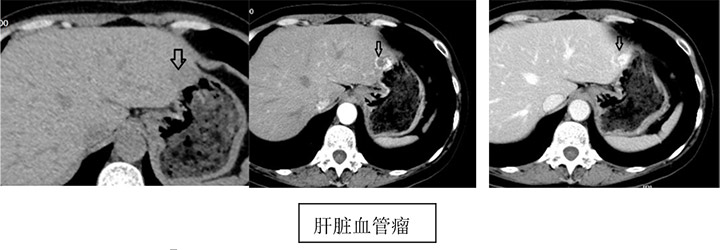

相信很多患者在不同的医院或多或少都遇到过这样问题。且听我来给你细说,CT和MRI具有很高的密度和空间分辨率,但是很多病变在平扫图像上与周围的组织和器官没有明显的密度和信号差异,很难显示出病灶或小肿瘤的范围和形态,需要静脉引入特定的造影剂,人为增加病变和正常组织、器官的密度以及信号差异,以及病变自身的强化方式等可以清晰显示平扫不能诊断的病灶。比如CT平扫发现肝内有个稍低密度病灶,想知道这到底是良性的(肝囊肿、肝血管瘤)还是恶性的(肝癌),毕竟定性诊断对病人的治疗方法非常重要,如果我们进一步做增强扫描,那么诊断医生根据更加全面的影像资料就比较容易诊断了。